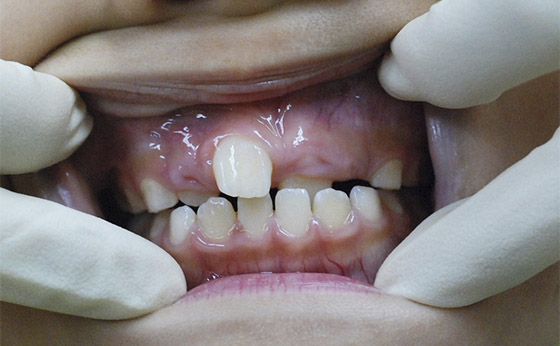

症例03 - ムーシールドによる歯列矯正

途中経過01

5歳の女の子、来院時、ご覧のような反対咬合。

下の歯が上の歯に逆に被さっています。ムーシールドという矯正装置を夜寝るときだけ装着しました。